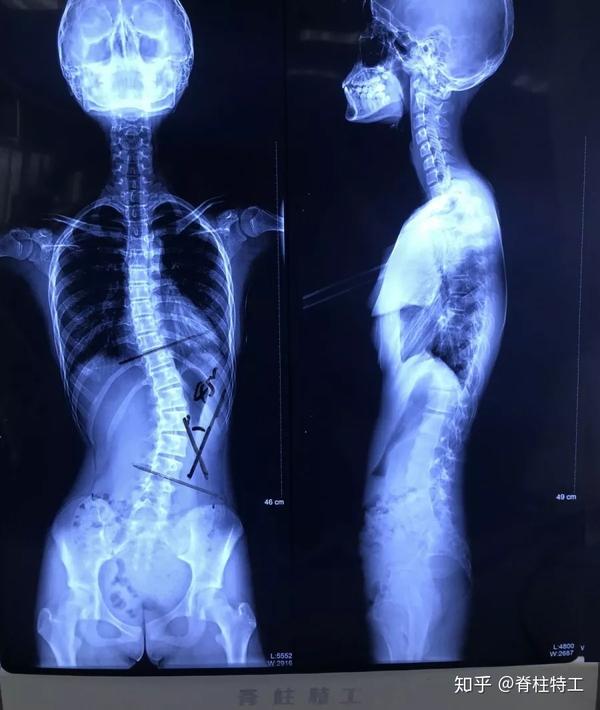

贫困少年脊柱侧弯超过100度每天进行十多个小时牵引治疗

超过90度我们就叫重度脊柱侧弯,超过100度是极重脊柱侧弯